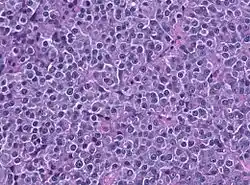

Description de l'image PRL HE histology.jpg.

Le prolactinome est une tumeur bénigne (adénome) de l'hypophyse (sécrétant de la prolactine). Il en résulte un excès de prolactine qui peut être ajusté par exemple par la bromocriptine (agoniste de la dopamine). Il apparaît surtout chez les jeunes femmes[1].